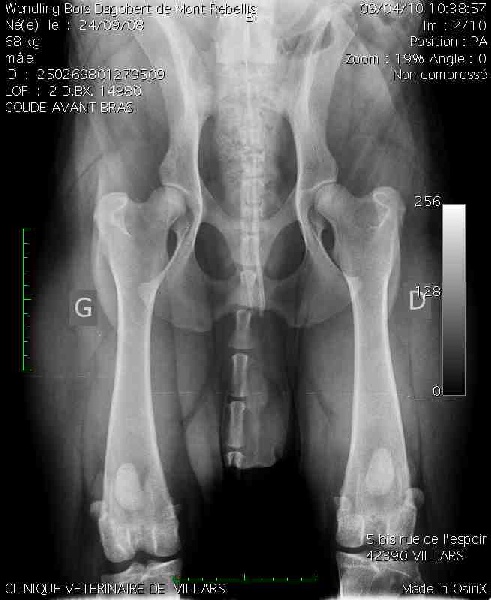

RADIO HANCHE